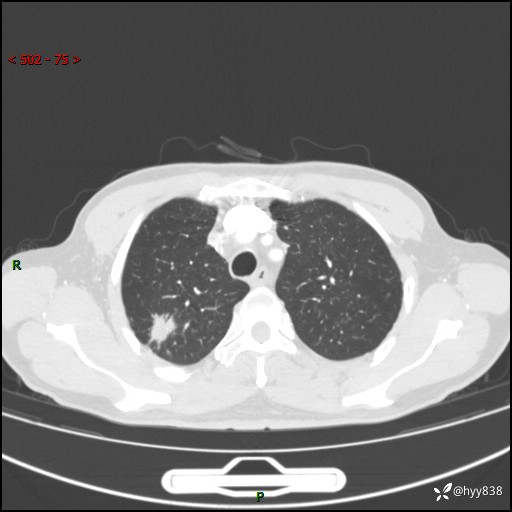

69岁/男,发现肺部病变6天。该有的征象都有,肉芽肿 VS 肿瘤,一念之间---(有结果)

主诉:发现肺部病变6天。

现病史:患者6天前于我院泌尿外科住院,住院期间行胸部CT检查,提示“肺部病变”,患者无畏寒、发热、盗汗、咳嗽、咳痰、咯血、胸痛、呼吸困难,无反酸、腹痛、腹泻、头痛、头晕等不适。未予特殊处理,现为进一步诊治,门诊以“肺肿物”收入我科。 患者本次起病以来,精神食欲尚可,大小便正常,体力及体重无明显变化。

胸部CT平扫+增强